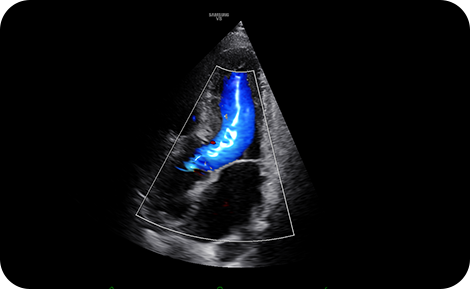

Show blood flow in vessels

in a 3D like display

LumiFlow™ is a function that visualizes blood flow in 3 dimensional-like to help understand the structure of blood flow and small vessels intuitively.

Color imaging : LumiFlow™

Apical 3 chamber color with LumiFlow™